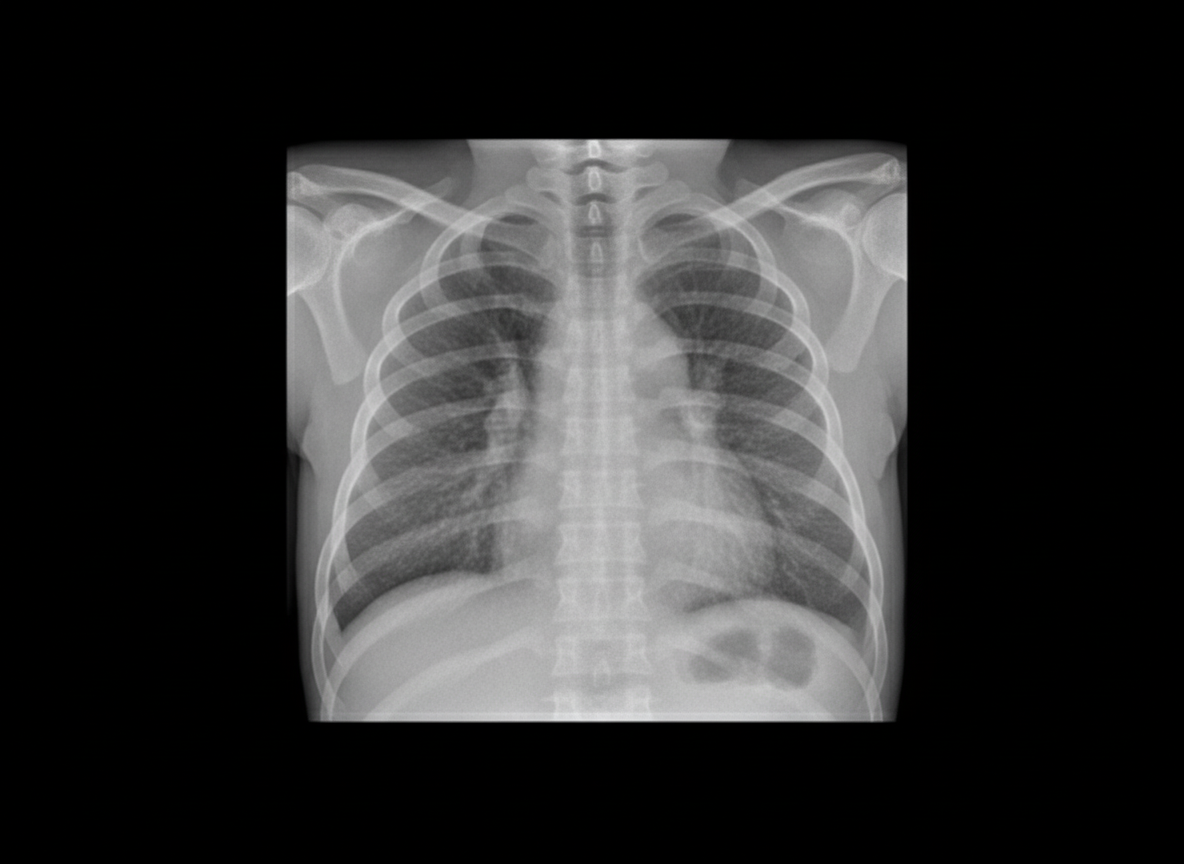

A neonate born at 34 weeks gestation with premature rupture of membranes undergoes a chest X-ray. Which of the following is LEAST likely to be considered in the differential diagnosis of the findings on the chest X-ray?

Explanation: ***Ventricular septal defect*** - **VSD** primarily causes **cardiomegaly** and **pulmonary plethora** on chest X-ray, not the typical respiratory distress patterns expected in a premature neonate. - The chest X-ray findings in this clinical scenario would more likely show **pulmonary parenchymal changes** rather than cardiac abnormalities. *Congenital pneumonia* - **Premature rupture of membranes (PROM)** significantly increases the risk of **ascending bacterial infection** leading to congenital pneumonia. - Chest X-ray typically shows **bilateral infiltrates**, **consolidation**, or **reticulogranular opacities** similar to other neonatal lung diseases. *Hyaline membrane disease* - **Prematurity at 34 weeks** places this neonate at high risk for **surfactant deficiency** causing hyaline membrane disease (respiratory distress syndrome). - Classic chest X-ray findings include **reticulogranular opacities**, **air bronchograms**, and **low lung volumes**. *Congenital alveolar proteinosis* - Presents with **bilateral pulmonary infiltrates** and **reticulogranular pattern** on chest X-ray, mimicking other neonatal respiratory conditions. - Can cause **respiratory distress** in neonates and appears radiographically similar to **hyaline membrane disease** or **congenital pneumonia**.